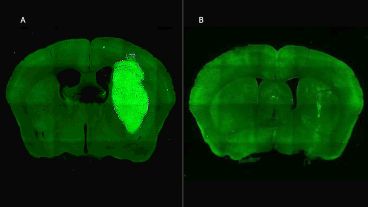

En estudios in vivo, el equipo liderado por Candolfi utilizó ratones inoculados en el cerebro con neuroesferas que contienen lesiones características de los tumores humanos que fueron desarrollados por el laboratorio de la científica argentina y colaboradora del estudio María Castro en la Universidad de Michigan, en Estados Unidos. Para tratar los tumores in vivo, los equipos de Candolfi y de la también científica del Conicet Flavia Zanetti, del Instituto de Ciencia y Tecnología César Milstein (Conicet- Fundación Pablo Cassará), desarrollaron un vector adenoviral que expresa la molécula o péptido P60 al interior de las células tumorales.

“Esta estrategia permite la expresión sostenida de P60 en la zona del tumor, facilitando la terapia y reduciendo la probabilidad de efectos colaterales sistémicos. Una inyección intratumoral del vector inhibió el crecimiento del tumor y mejoró notablemente la respuesta a la quimioterapia, llevando a la erradicación del tumor y sobrevida a largo plazo en un tercio de los ratones con tratamiento combinado”, afirma Candolfi. Y agrega: “No observamos efectos neurotóxicos con ninguno de los tratamientos empleados, por lo tanto, esta estrategia tendría buen perfil de seguridad para tratar estos tumores”.